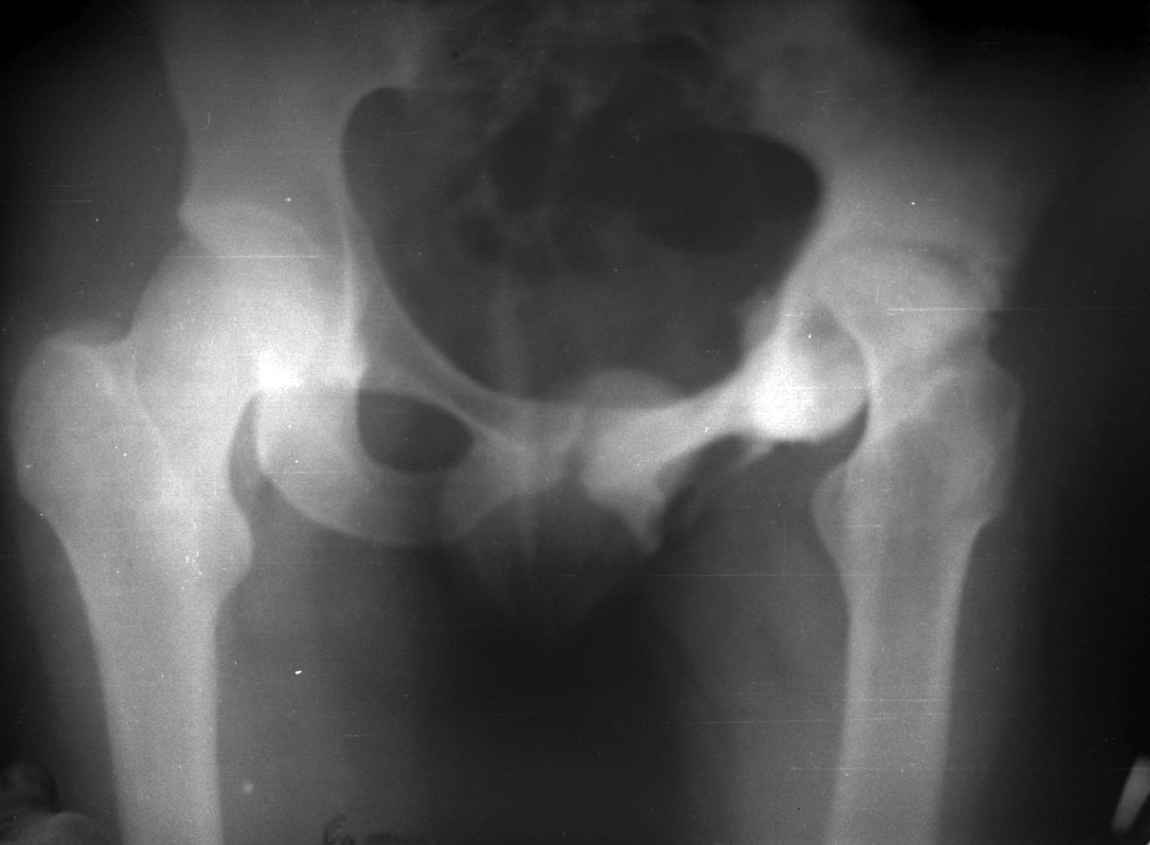

.........наверное не повезло. Но иногда это выход и очень хороший. М., 21 года спрыгнул в Армии с машины с исходом в гнойный коксит, свищевой формой в течении 1,5 лет. Операция проведена в 1988 году. результат хороший и сейчас и мы с пациентом хорошие приятели (Рентг-гр и фото прилагаю).

Еще один раз произведена реконструкция проксимального отдела юноше 17 лет с посл гематог остеомиелита тотальным дефектом проксимального отдела бедра и укорочением 16 см.(проксим отдел в виде "сосульки"). Произведена одноэтапная последовательная реконструкция, удлинение в с/з, затем в н/з. Рентгенограммы к сожалению утеряны.

Результат, поверьте, фантастический. Колено почти не пострадало. Сейчас сам удивляюсь, как хорошо получилось. РПО по Илизарову - Выход из ситуации иногда единственный, и хороший почти всегда, но трудоемкий для врача и тяжелый - пролонгированно для больного(в этом то и "собака порыта").

Вы немножко не поняли предмета нашего разговора. На представленных Вами Р-граммах речь идет о вальгизирующих остеотомиях, скорее всего в

комбинации с разгибанием... Никто и не оспаривает полезность этих остеотомий, мой личный опыт свидетельствует о том, что даже при

выраженной стадии коксартроза у лиц молодого возраста существенно снижается болевой с-м, ремиссия иногда достигает 12-16 лет, а там уже не

грех и протез поставить.

На обсуждение поставлен вопрос об эффективности опорной остеотомии по Илизарову (как правило), при врожденных вывихах бедра. Почувствуйте разницу...